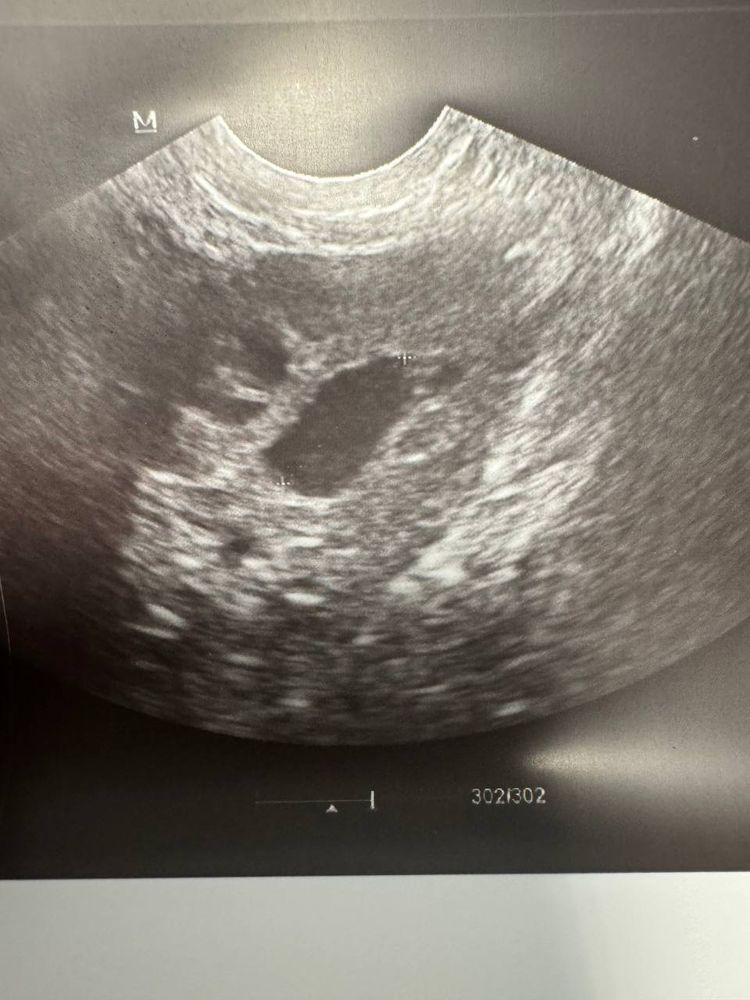

23.10.2024 - 7 день цикла, фолликул выглядит так(с разных ракурсов) и эндометрий 6,5

При этом всем, он такой же странной формы - как был в октябре (овальный такой больше, не круглый). Так вот, у меня вопрос - что это, блин, такое? Это тот же самый фолликул? Киста? Но кисты вроде от 30 мм, а у меня был 23 и теперь 16…